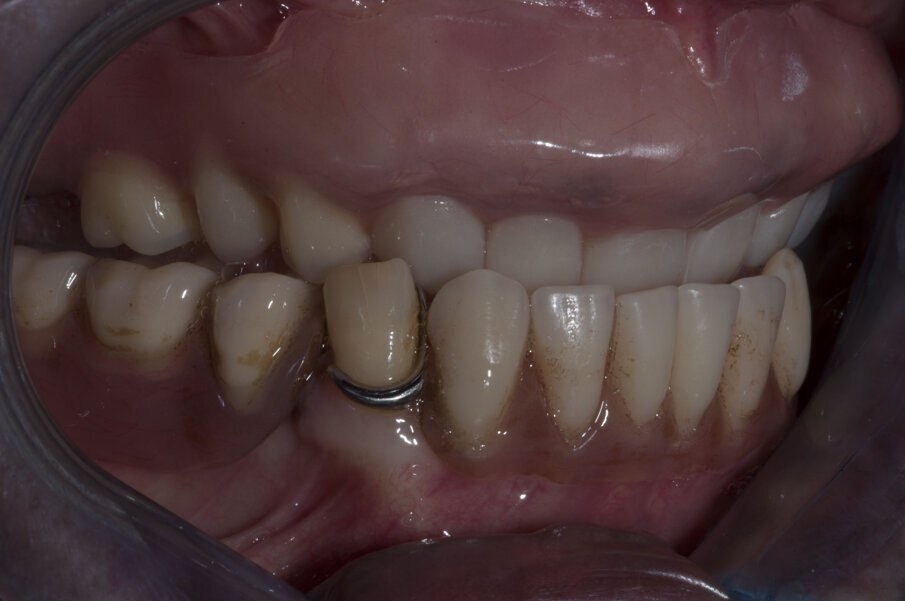

Grazie a questo tipo di pianificazione il software produce una guida chirurgica che viene stampata da una stampante 3D e consente al chirurgo di operare con tecnica “flapless” cioè senza la necessità di aprire dei lembi e causare un maggiore traumatismo al paziente. La guida chirurgica trasparente viene provata in bocca al paziente prima dell’intervento chirurgico per testare la sua stabilità e precisione nel rapporto con i tessuti molli (Figg. 20, 21). In questo caso specifico si era pianificato di utilizzare un nuovo approccio con degli impianti e componenti protesiche particolari, la tecnica “Smart fix” di Astra Tech Implant (Dentsply Sirona) (Figg. 22-25).